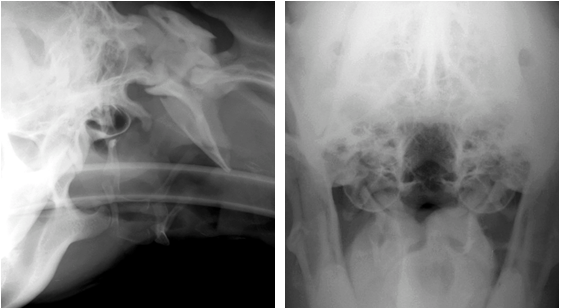

How can radiography help diagnose otitis media?

What can be seen here?

CT (X-ray computed tomography)

Can see bony changes after chronic pseudomonas otitis